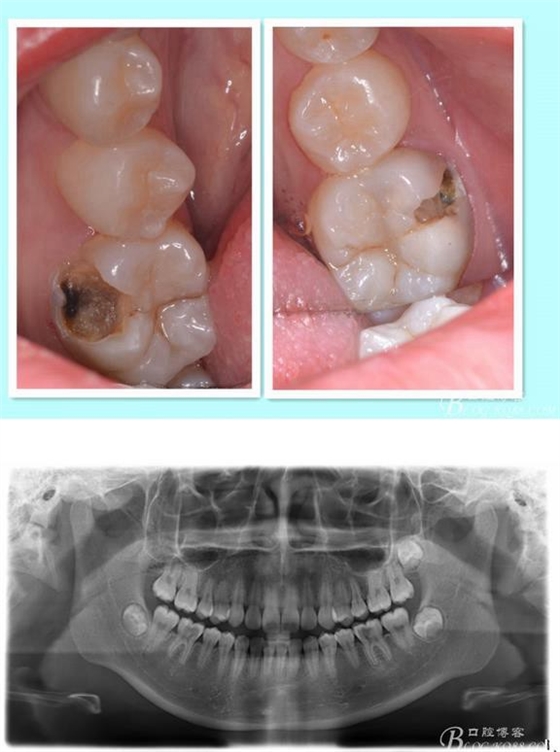

主訴:雙側(cè)下后牙疼痛一月余

病史:近一個(gè)月雙側(cè)下后牙疼痛,自發(fā)性 陣發(fā)性鈍痛,進(jìn)食嵌塞加重,求診

查:雙側(cè)下6頰HE面齲壞 探診疼痛 冷熱刺激 遲反應(yīng)疼痛 叩診(-)頰側(cè)齲壞平齦

X線:雙側(cè)下6 齲壞已接近髓腔

診斷:雙側(cè)下6 慢性牙髓炎

治療方案:雙側(cè)RCT+CAD-CAM

這里我單做右側(cè)的詳細(xì)步驟